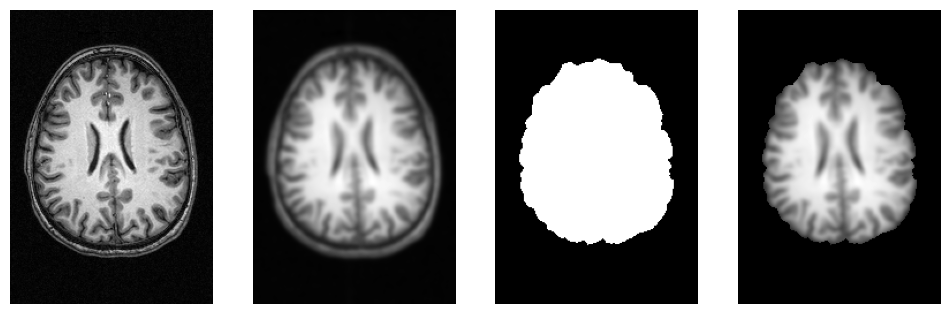

# Plot original input file

plotting.plot_anat(input_file, title='BET input', cut_coords=(10,10,10),

display_mode='ortho', dim=-1, draw_cross=False, annotate=False);

# Plot skullstripped output file (out_file) through the outputs property

plotting.plot_anat(res.outputs.out_file, title='BET output', cut_coords=(10,10,10),

f = plt.figure(figsize=(12, 4))

for i, img in enumerate([input_file,

opj(wf_work_dir, "smoothflow/smooth/sub-01_T1w_smooth.nii.gz"),

opj(wf_work_dir, "smoothflow/skullstrip/sub-01_T1w_brain_mask.nii.gz"),

opj(wf_work_dir, "smoothflow/mask/sub-01_T1w_smooth_masked.nii.gz")]):

f.add_subplot(1, 4, i + 1)

plot_slice(img)